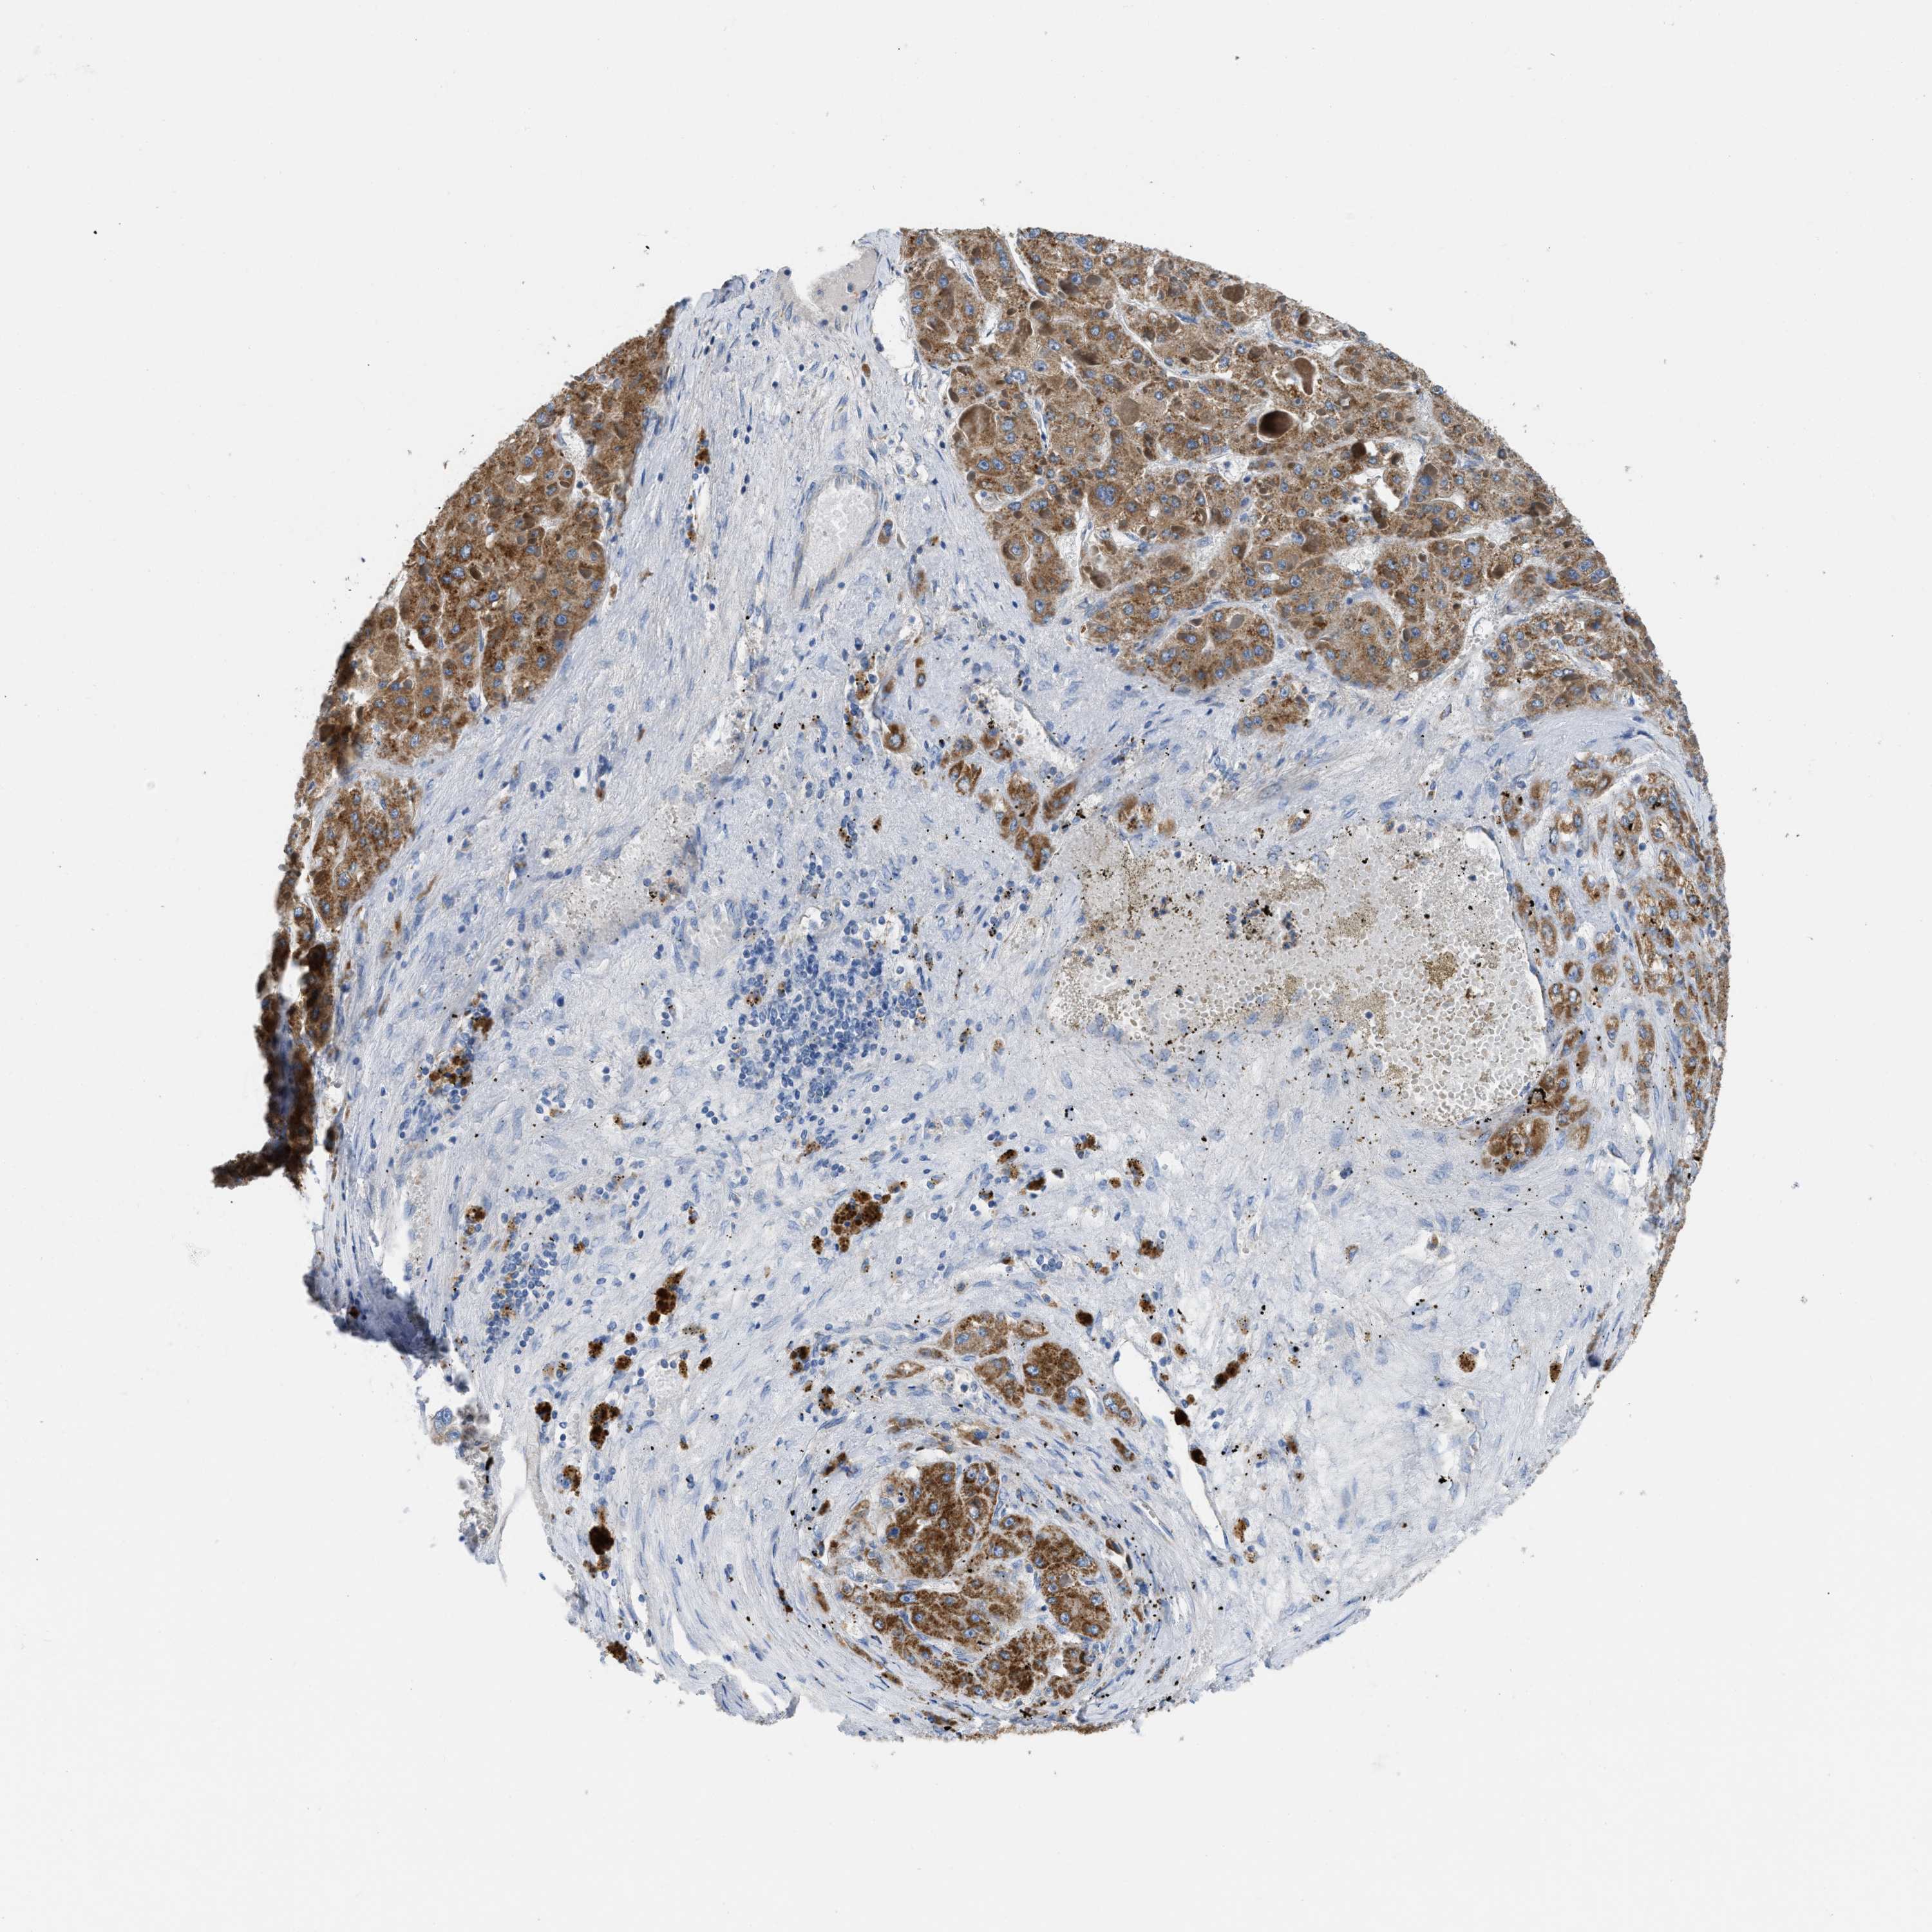

LIVER CANCER - Protein expressioni

A mouse-over function shows sample information and annotation data. Click on an image to view it in a full screen mode. Samples can be filtered based on level of antibody staining by selecting one or several of the following categories: high, medium, low and not detected. The assay and annotation is described here.

Note that samples used for immunohistochemistry by the Human Protein Atlas do not correspond to samples in the TCGA dataset.

Antibody stainingi

Antibody staining in the annotated cell types in the current human tissue is reported as not detected, low, medium, or high, based on conventional immunohistochemistry profiling in selected tissues. This score is based on the combination of the staining intensity and fraction of stained cells.

Each image is clickable and will lead to virtual microscopy that enables deeper exploration of all samples and also displays staining intensity scores, fraction scores and subcellular localization as well as patient and tissue information for each sample.

Antibody HPA018997

Staining

High

Medium

Low

Not detected

Intensity

Strong

Moderate

Weak

Negative

Quantity

>75%

75%-25%

<25%

None

Location

Nuclear

Cytoplasmic/membranous

Cytoplasmic/membranous,nuclear

Cholangiocarcinoma

Carcinoma, Hepatocellular, NOS